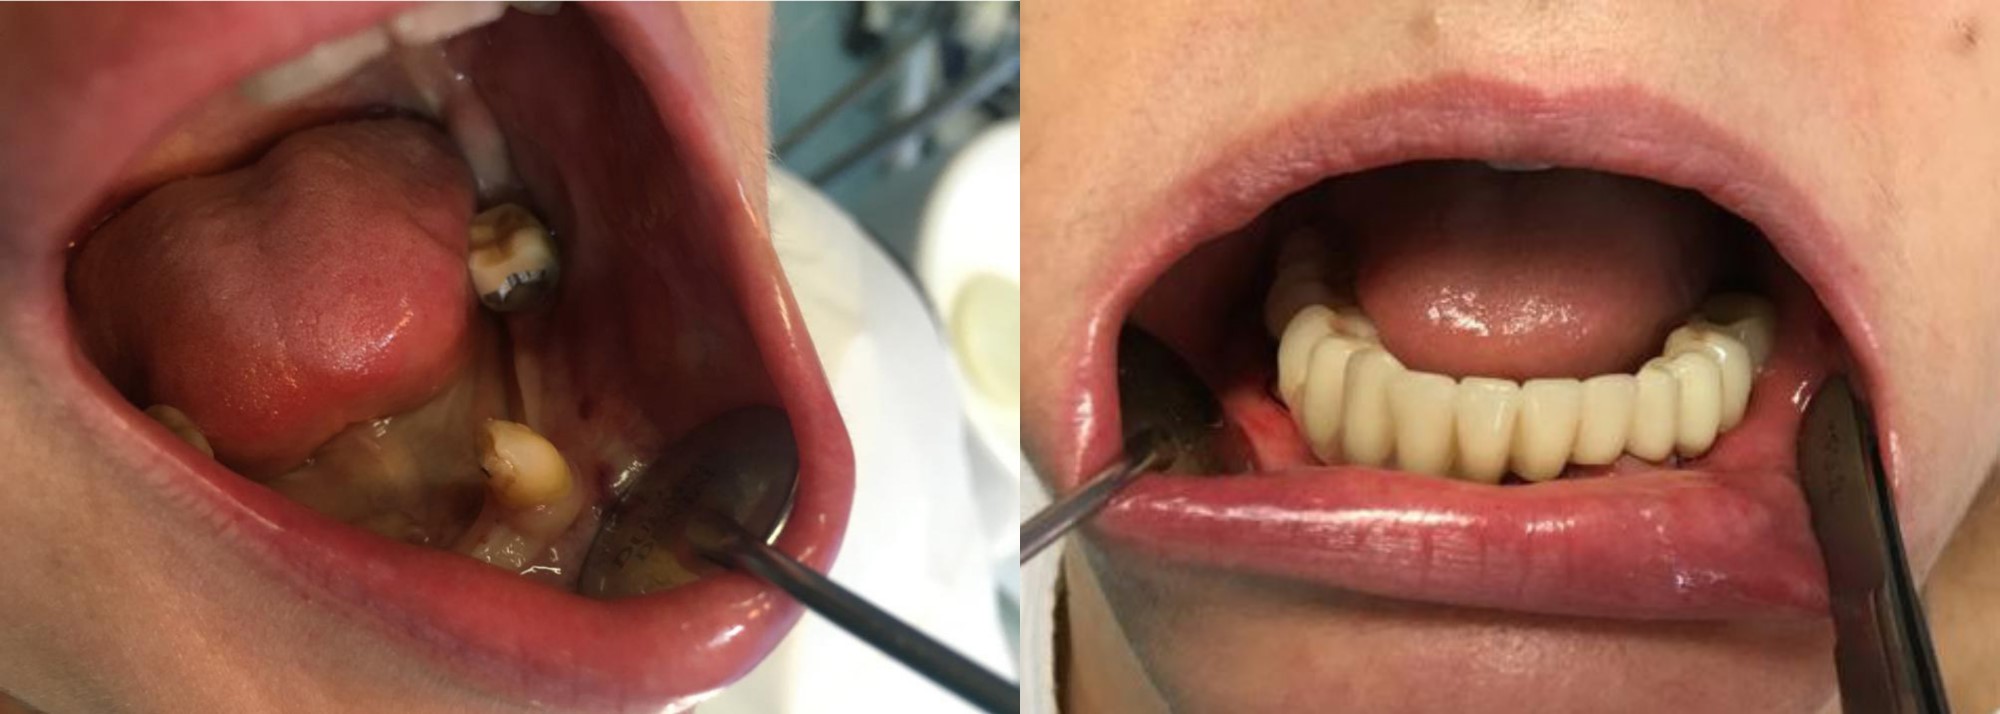

Estrazione di tutti i denti, inserimento di 6 impianti e protesizzazione a distanza di 24 ore